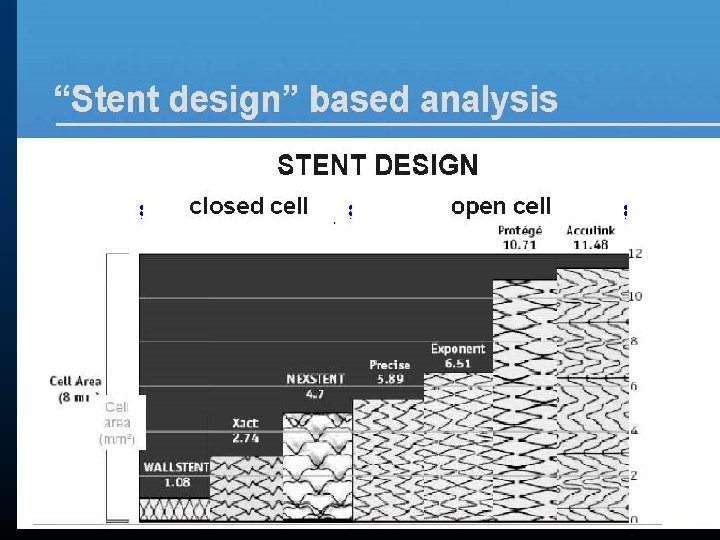

“Stent design” based analysis ALL EVENTS Total Symptomatic Asymptomatic population n/N % Closed 51/2242 2. 3% 21/934 2. 2% 30/1308 2. 3% Open 39/937 4. 2% 27/383 7. 0% 12/554 2. 2% TOTAL 90/3179 2. 8% 48/1317 3. 6% 42/1862 2. 6%

“Stent design” based analysis All events: open vs. < closed cell Odds Ratio 95% C. I. Total population 1. 876 [1. 227 -2. 868] Symptomatic population 3. 297 [1. 840 -5. 908] Asymptomatic population 0. 943 [0. 479 -1. 856]

“Stent design” based analysis LATE EVENTS Total Symptomatic Asymptomatic population n/N % Closed 29/2242 1. 3% 12/934 1. 3% 17/1308 1. 3% Open 32/937 3. 4% 24/383 6. 3% 8/554 1. 4% TOTAL 61/3179 1. 9% 36/1317 2. 7% 25/1862 1. 3%

“Free cell area” based analysis ALL EVENTS Total Symptomatic Asymptomatic population n/N % < 2. 5 mm² 48/2107 2. 3% 20/882 2. 3% 28/1225 2. 3% 2. 5 -5 mm² 3/135 2. 2% 1/52 1. 9% 2/83 2. 4% 5 -7. 5 mm² 16/327 4. 9% 10/155 6. 5% 6/172 3. 5% > 7. 5 mm² 23/610 3. 8% 17/228 7. 5% 6/382 1. 6% TOTAL 90/3179 2. 8% 48/1317 3. 6% 42/1862 2. 6%

“Free cell area” based analysis LATE EVENTS Total Symptomatic Asymptomatic population n/N % < 2. 5 mm² 26/2107 1. 2% 11/882 1. 2% 15/1225 1. 2% 2. 5 -5 mm² 3/135 2. 2% 1/52 1. 9% 2/83 2. 4% 5 -7. 5 mm² 11/327 3. 4% 8/155 5. 2% 3/172 1. 7% > 7. 5 mm² 21/610 3. 4% 16/228 7. 0% 5/382 1. 3% TOTAL 61/3179 1. 9% 36/1317 2. 7% 25/1862 1. 3%

“Free cell area” based analysi. S Late events: Total population Free cell area Odds Ratio 95% C. I. 2. 5 -5 vs. < 2. 5 mm² 1. 869 [0. 557 -6. 267] 5 -7. 5 vs. < 2. 5 mm² 2. 681 [1. 310 -5. 490] > 7. 5 vs. < 2. 5 mm² 2. 963 [1. 653 -5. 313]

“Free cell area” based analysi. S Late events: Symptomatic population Free cell area Odds Ratio 95% C. I. 2. 5 -5 vs. < 2. 5 mm² 1. 553 [0. 197 -12. 261] 5 -7. 5 vs. < 2. 5 mm² 4. 309 [1. 705 -10. 893] > 7. 5 vs. < 2. 5 mm² 5. 976 [2. 733 -13. 065]

“Free cell area” based analysi. S Late events: Asymptomatic population Free cell area Odds Ratio 95% C. I. 2. 5 -5 vs. < 2. 5 mm² 1. 992 [0. 448 -8. 860] 5 -7. 5 vs. < 2. 5 mm² 1. 432 [0. 410 -4. 998] > 7. 5 vs. < 2. 5 mm² 1. 070 [0. 386 -2. 963]

Conclusion • Different complication rates between stents • Almost entirely explained by symptomatic population • Late complication event rates are – Highest for the open cell types – Increase with increasing free cell area • Prospective randomised trials required to further investigate the importance of free cell area • For the time being, stents with a small free cell area should be used in symptomatic patients